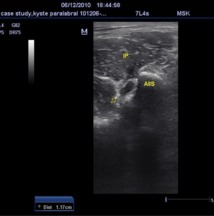

Si le diagnostic est évoqué, il faut garder à l’esprit que l’échographie met rarement en évidence une fissure du bourrelet cotyloïdien. Néanmoins, les kystes paracotyloïdiens sont des signes indirects de fissure très souvent associés à cette lésion. La reconnaissance de ces kystes est capitale pour orienter les investigations complémentaires. L’échographie permet de les identifier facilement, comme vous pouvez le voir sur la photo jointe.

Une autre difficulté est liée au diagnostic différentiel entre les kystes paracotyloïdien et les bursites du psoas dont l’apparence échographique peut être similaire. Il faut noter qu’aucune investigation ne présente une sensibilité et une spécificité suffisante pour affirmer le diagnostic de fissure paracotyloïdienne de manière définitive pour tous les cas. Actuellement, l’arthro-IRM est l’examen le plus indiqué et il est important de le proposer lorsque des images kystiques sont identifiées à l’échographie.

Conclusion: le rôle de l’échographie peut-être primordiale dans la suspicion d'une fissure du bourrelet cotyloïdien en recherchant un signe indirect lié à une complication de cette fissure, le kyste paracotyloïdien.